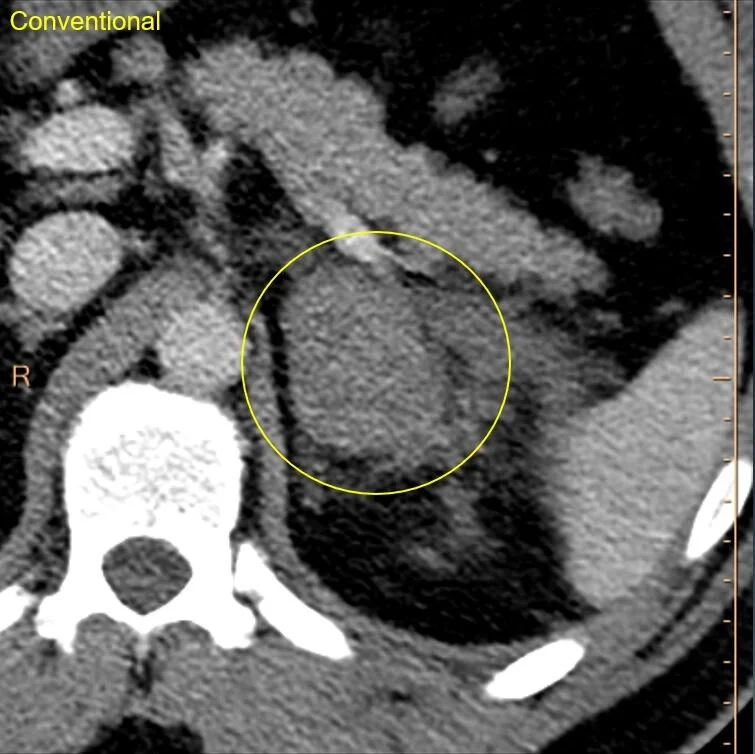

Young M presented to the ED after trauma. CT scan was obtained showing a large L adrenal mass. Small adjacent fat stranding too.

Conventional CT: Large left adrenal mass, about 60 HU. Typically read as “indeterminate”.